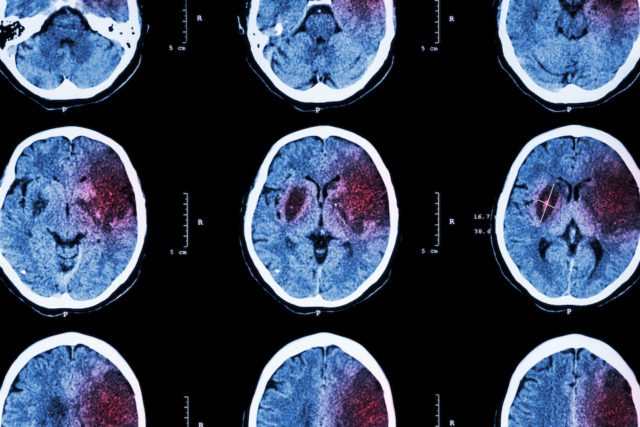

Компьютерная томография головного мозга

Подтверждение диагноза возможно только с помощью визуальных методов:

- компьютерная томография определяет размеры кровоизлияния, как в субарахноидальном пространстве, так и в паренхиме. Метод выявляет отек тканей, кровоизлияние в желудочки и гидроцефалию;

- магнитно-резонансная томография необходима при выявлении гематом малого размера в структурах заднего мозга (мост, продолговатый мозг), артериовенозных мальформаций без применения контраста в отличие от КТ.

Геморрагический инсульт на КТ в первые часы визуализируется с помощью плотного сгустка.